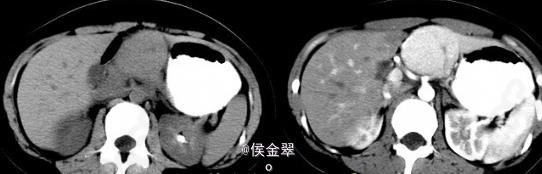

患者,女,30岁,因反复上腹部疼痛不适1年前来就诊。

患者查体发现上腹疼痛不适,其余正常 辅查CT:平扫为低密度占位,增强后期出现快速强化。

肝脏局灶性结节性增生 处理:观察随访如肿瘤生长则切除